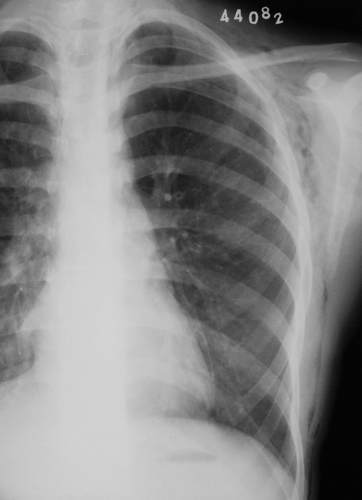

左侧胸壁、腋窝、颈部及右侧颈部皮下软组织内示斑片状、条状低密度气体影,四天后复查片明显吸收好转。